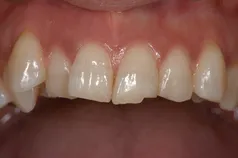

[症例2]

治療前は前歯の間がすいているため、人前で笑えないなどのコンプレックスを持たれていました。

ホワイトニング後、前歯4本をラミネート・ベニアで治療することで引き締まった口元になり、笑顔が多くなりました。

- 治療期間:2ヶ月

- 治療費:45万円

- 治療回数:4回